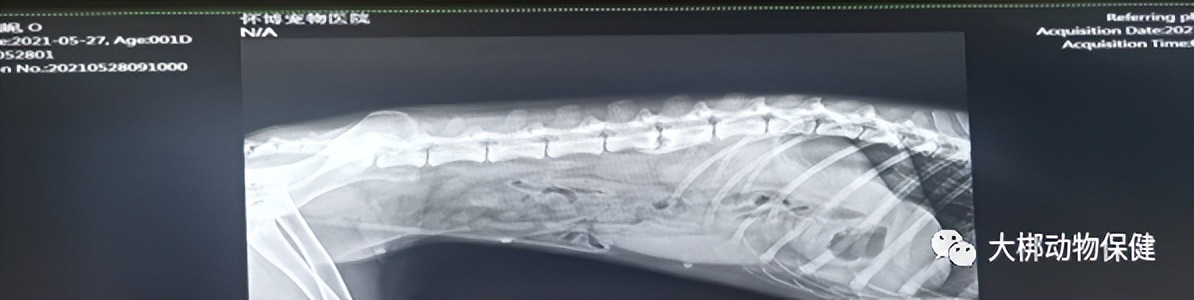

医生进行一般性检查发现: 触诊腹部紧张有疼痛感,结膜炎颜色正常、口腔颜色偏白,肌肉状态良好,对食物无兴趣,喜卧不动。血常规无异常,犬C反应蛋白轻度升高,犬胰腺炎指标升高,DR影像显示胃肠气体,无高密度异物。